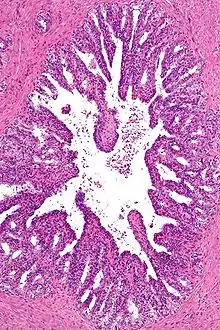

Prostate

La prostate est un organe glandulaire et fibromusculaire contenant une portion de l'urètre. Elle est située dans le petit bassin, entre la symphyse pubienne en avant, le rectum en arrière, la vessie en haut et le périnée en bas. Elle sécrète une partie du sperme dans l'urètre.

- le cancer de la prostate est un cancer fréquent touchant la prostate, une glande de l'appareil reproducteur de l'homme. Le cancer se développe à partir des tissus de la prostate quand des cellules y mutent et se multiplient de façon incontrôlée. Celles-ci peuvent ensuite s'étendre (se métastaser) en migrant de la prostate jusqu'à d'autres parties du corps, particulièrement les os et les ganglions lymphatiques du pelvis. Le cancer de la prostate survient indépendamment de l'hypertrophie bénigne de la prostate (HBP), ou adénome prostatique.